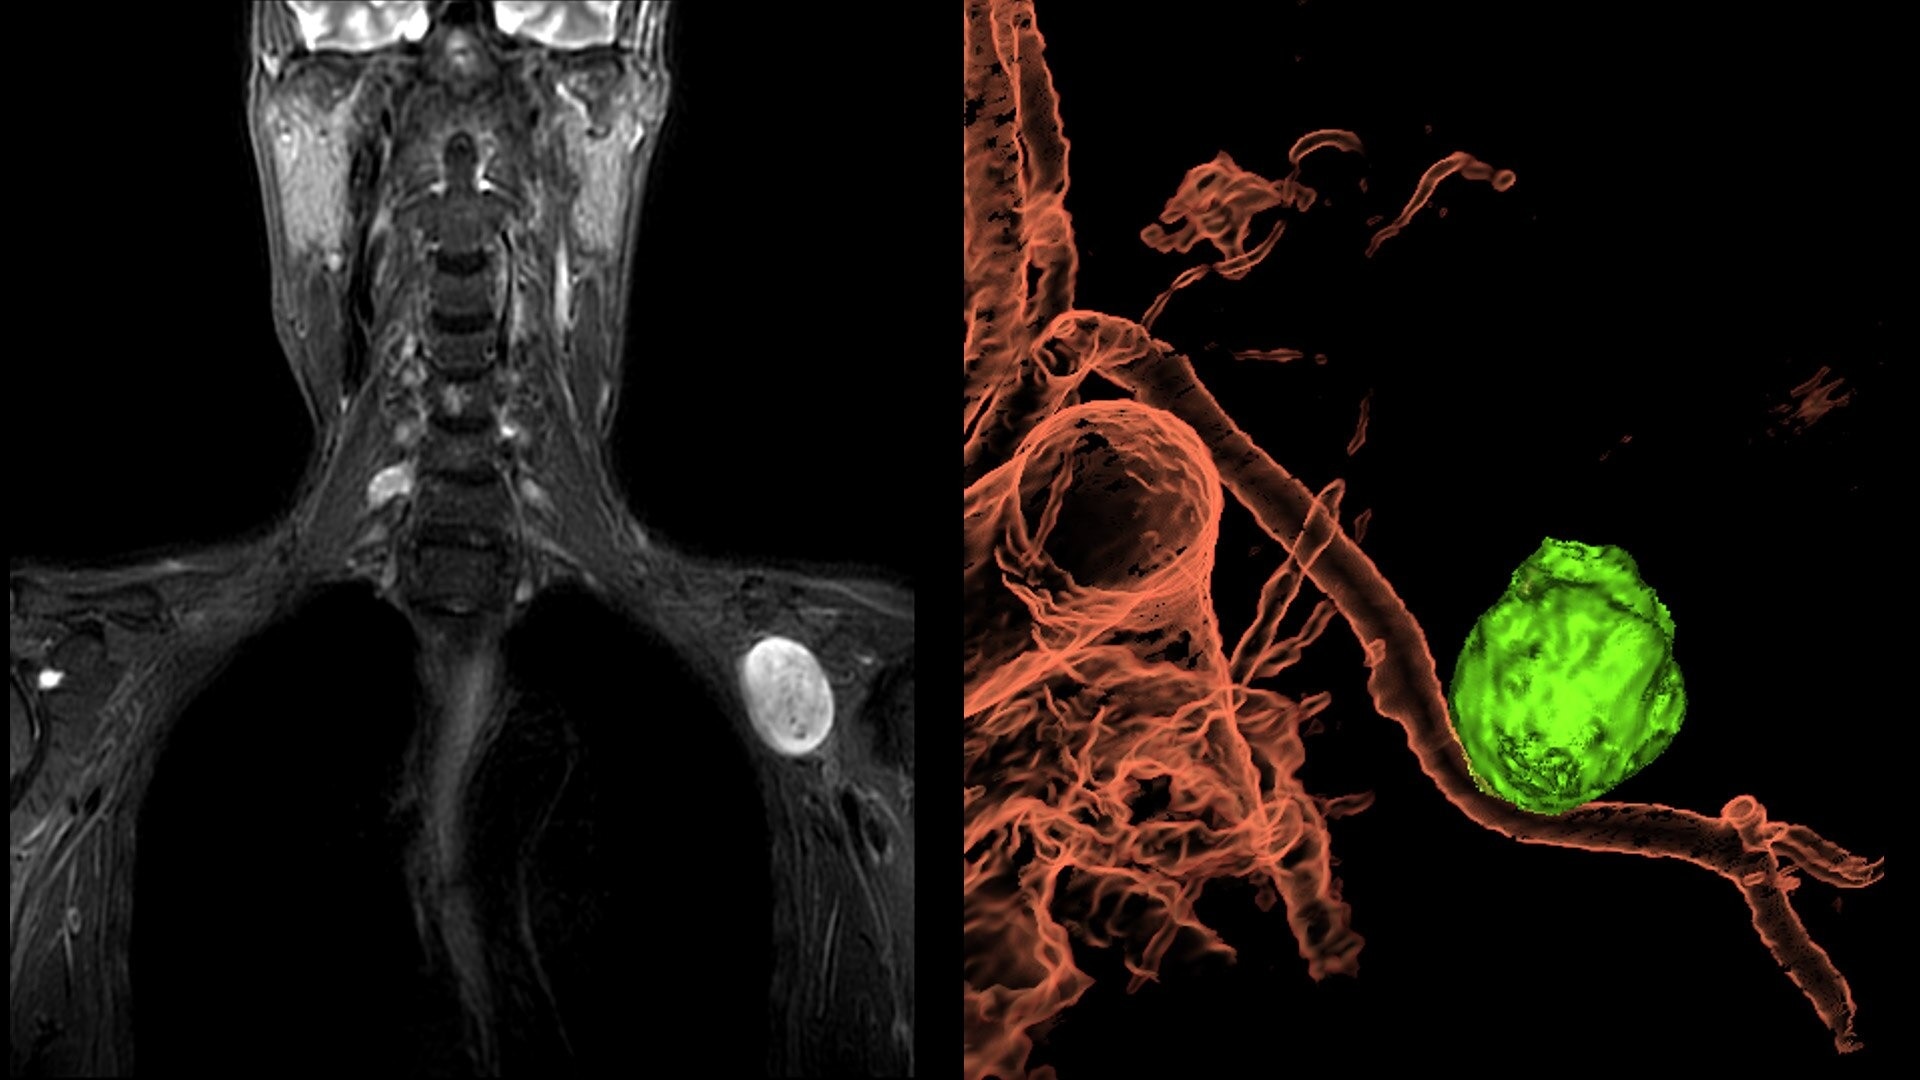

The shape of the MRI coil no longer determines what you can do with it. Wrap it around a knee for a complete knee image. Drape it over the patient's body. With an adaptive AIR™ Coil that is light, form fitting and easy to position, it’s the closest you can get to total positioning freedom with 360-degree coverage.

• 360 degrees of coverage for MSK imaging

• Positioning freedom with previously hard-to-scan anatomies

• 20-ch and 21-ch design to accommodate all patient sizes and anatomies